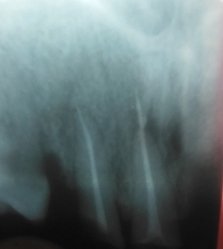

В подростковом возрасте мне сделали резекцию передних зубов из-за кисты. Но спустя примерно 15 лет над зубом образовался, на ощупь, шарик и очень неприятное напряжение под зубом. Я пошла к врачу, он отправил на снимок, но так и не смог мне помочь, и отправил к другому стоматологу, но попасть к нему я так и не смогла.

У вас так называемый рецидив. Обратитесь к хирургу, думаю, данный зуб придется удалить.